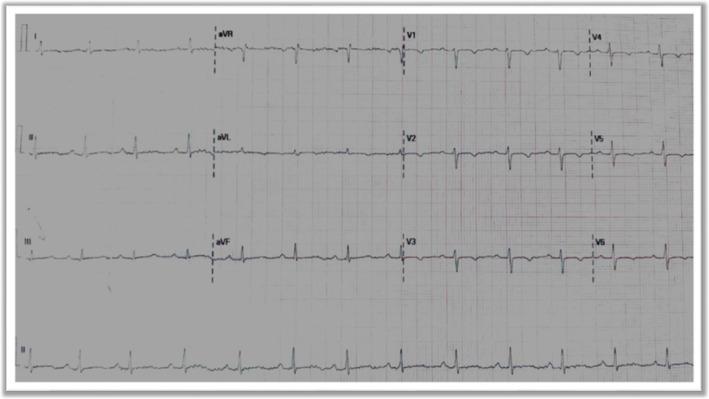

An aorto-cameral fistula (ACF) is a rare abnormal communication between the aorta and a cardiac chamber, often resulting from trauma, ruptured sinus of Valsalva aneurysms, infective endocarditis, aortic dissection, or iatrogenic causes. Clinical presentations vary from asymptomatic cases to severe hemodynamic compromise, including heart failure, arrhythmias, and sudden cardiac death. We present a 17-year-old female with exertional dyspnea and fatigue, 9 years after a penetrating chest trauma. Transthoracic echocardiography and cardiac CT revealed an 8 mm fistulous connection between the right sinus of Valsalva and the right ventricular outflow tract. Surgical repair under cardiopulmonary bypass successfully closed the defect with 5-0 Prolene sutures, confirmed intraoperatively without residual shunting or aortic valve dysfunction. The patient recovered uneventfully and was discharged on postoperative day four. This case highlights the diagnostic challenges of chronic traumatic ACF and emphasizes the importance of multimodal imaging for early detection and timely surgical intervention to prevent long-term hemodynamic deterioration. Given the potential for delayed complications, clinicians should maintain a high index of suspicion for post-traumatic cardiac fistulas, even years after the initial injury.

主动脉-心腔瘘(ACF)是一种罕见的主动脉与心腔之间的异常连通,通常由外伤、瓦氏窦瘤破裂、感染性心内膜炎、主动脉夹层或医源性原因引起。临床表现从无症状到严重的血流动力学障碍不等,包括心力衰竭、心律失常和心源性猝死。我们报告一例17岁女性,在胸部穿透伤9年后出现劳力性呼吸困难和疲劳。经胸超声心动图和心脏CT显示,瓦氏窦右窦与右心室流出道之间存在一个8毫米的瘘管连接。在体外循环下进行手术修复,成功地用5-0普罗林缝线闭合了缺损,术中证实无残余分流或主动脉瓣功能障碍。患者恢复顺利,术后第四天出院。该病例突出了慢性创伤性ACF的诊断挑战,并强调了多模态成像对于早期检测和及时手术干预以防止长期血流动力学恶化的重要性。鉴于可能出现延迟并发症,临床医生即使在初始损伤多年后,也应高度怀疑创伤后心脏瘘。